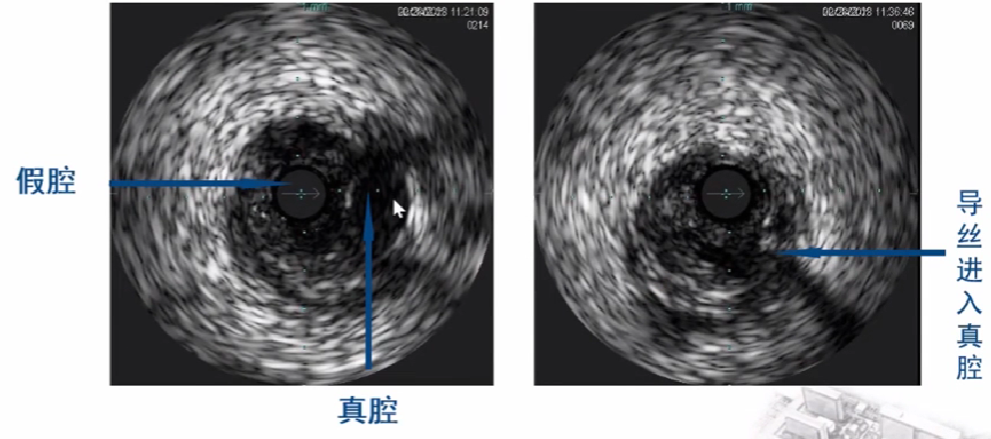

10、CTO介入治疗中超声鉴别真假腔